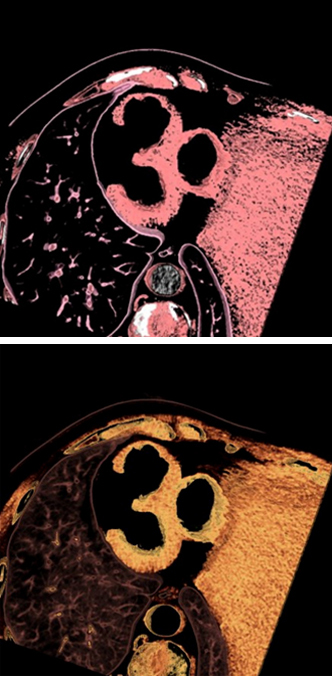

[금상] 심장 CT에서 찾은 30 (서울성모병원 장수연 교수님)

심장 구조 속에서 우연히 드러난‘30’의 형태를 포착했습니다. 30년간 이어진 학회의 발걸음을 축하합니다.